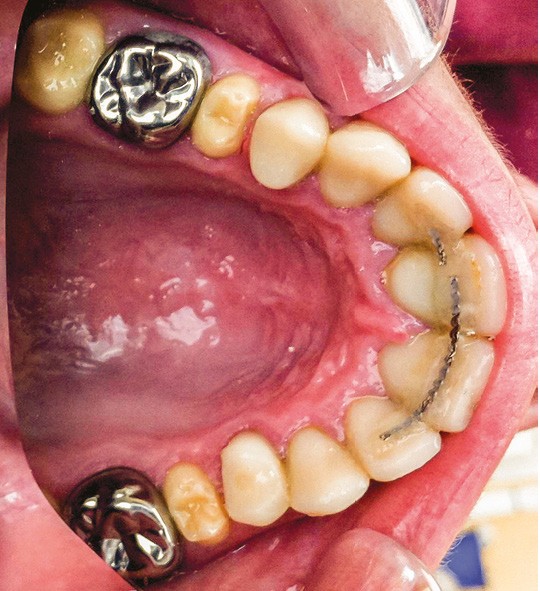

Une patiente âgée de 12 ans a été adressée au cabinet pour « une prise en charge complète sur le long terme » par son praticien traitant. Elle était accompagnée par sa mère. Elle présentait des couronnes transitoires en résine sur le secteur incisivo-canin au maxillaire ainsi que les premières prémolaires, des coiffes pédodontiques métalliques sur les premières molaires, une absence totale d’émail sur l’ensemble de la denture, à l’exclusion des bords libres des incisives mandibulaires (fig. 1 à 3). Le bloc incisivo-canin mandibulaire avait bénéficié de traitements radiculaires (fig. 4). Les incisives maxillaires présentaient des rhizalyses d’une importance significative (fig. 5 et 6). La patiente se plaignait d’hypersensibilités à la mastication et au brossage, la demande esthétique était forte.